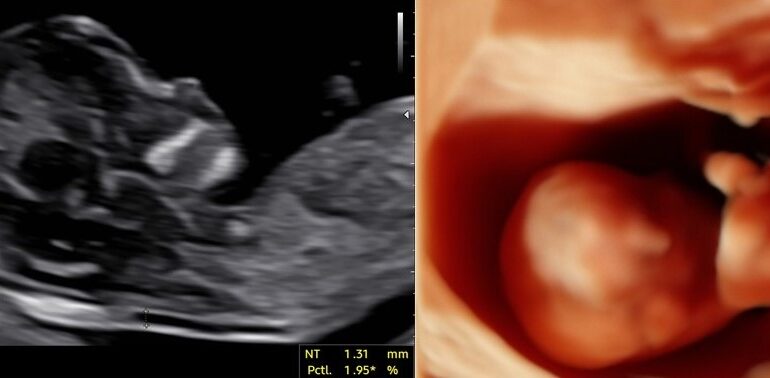

Licenci Fetal Medicine Foundation za presejanje v 11.-13. tednu nosečnosti (nuhalna svetlina) in za merjenje materničnega vratu z ocenjevanjem tveganja prezgodnjega poroda

Licenci Fetal Medicine Foundation za presejanje v 11.-13 tednu nosečnosti (nuhalna svetlina) in za merjenje materničnega vratu z ocenjevanjem tveganja prezgodnjega poroda

Tudi za nosečnice, ki imajo izbranega drugega ginekologa, izvajamo v okviru zdravstvenega zavarovanja preglede nuhalne svetline z dvojnim hormonskim testom (kombiniran test).

4D: …V ZD nimajo možnosti dati na usb, niti slikce niso lepe. Vem pa da to dr.Sava naredi super 🙂